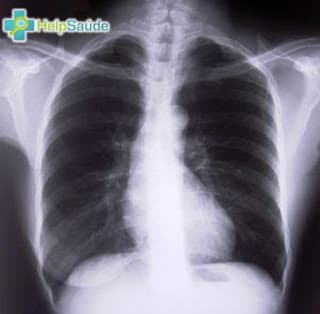

Pneumonia